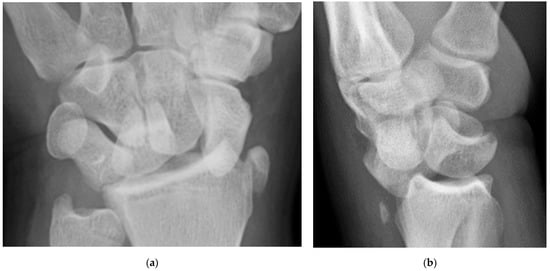

Figure 29. (a) PA wrist radiograph showing scapholunate dissociation, lunotriquetral dissociation, and radial styloid avulsion. (b) Lateral radiograph showing capitate dislocation. In addition to the PA radiograph, findings are consistent with a midcarpal dislocation, stage three perilunate injury.

Perilunate injury involves both intrinsic and extrinsic ligaments and results in a fairly predictable order of progression when the wrist is loaded in extension, ulnar deviation, and intercarpal supination. The typical history is a fall onto a dorsiflexed wrist (e.g., the FOOSH), and the injury progresses through four distinct stages depending on the magnitude of the traumatic force that it sustained. The first stage consists of scapholunate dissociation (Figure 27a). As the scapholunate joint is disrupted, the scapholunate and radioscaphocapitate ligaments are injured, causing volar scaphoid rotation with or without dorsal rotation of the lunate, and scapholunate joint widening (Figure 27b). The second stage consists of perilunate dislocation (Figure 28). In this stage, the scapholunate injury found in the first stage is still present, but as the force is increased, this trauma has extended to involve the capitolunate ligament, which then allows the capitate to be dislocated. The third stage is again a progression of the prior stages in which the lunotriquetral ligament is disrupted in addition to the findings of the second stage. Neither the capitate nor lunate is aligned with the distal radius, often referred to as a midcarpal dislocation. There is also interval development of widening/malalignment of the lunotriquetral and triquetrohamate joints, which is frequently associated with a volar triquetral fracture (Figure 29). The fourth and final stage of injury results in tears/disruptions of all the ligaments surrounding the lunate, including the dorsal radiocarpal ligament, resulting in palmar dislocation of the lunate (lunate dislocation). On PA radiographs, the lunate shows the classic “piece-of-pie” sign, and on the lateral view, there is a “tipped teacup” appearance (Figure 30).